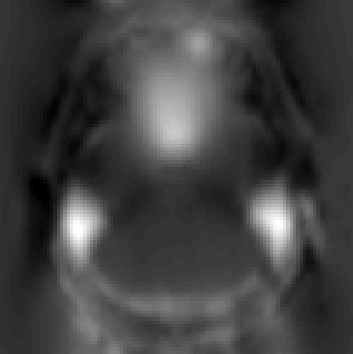

We next take a look at my_field.nii.gz (the output from --fout) to see what topup thinks the off-resonance field looks like.

--fout output

which has been scaled so that black corresponds to -50Hz and white to 150Hz. This looks like a reasonable off-resonance field with higher than "expected" field above the ear-canals and the roof of the sinuses.